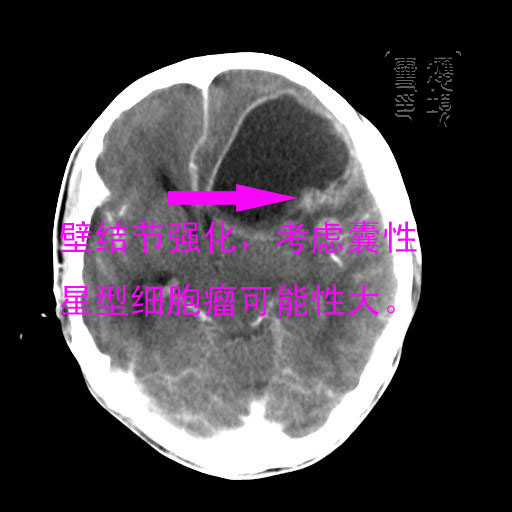

见环形,结节样强化,考虑囊性星型细胞瘤。

考虑囊性星型细胞瘤,ct征象大囊小结节.

左额叶囊实性占位,以囊性为主,并见明显强化不规则壁结节,占位效应明显,首先考虑是囊性星形细胞瘤.

谢谢楼上的朋友们!

结果已经在最后一幅图片内,感兴趣的,另存此图用记事本打开,往下拉就可看到。